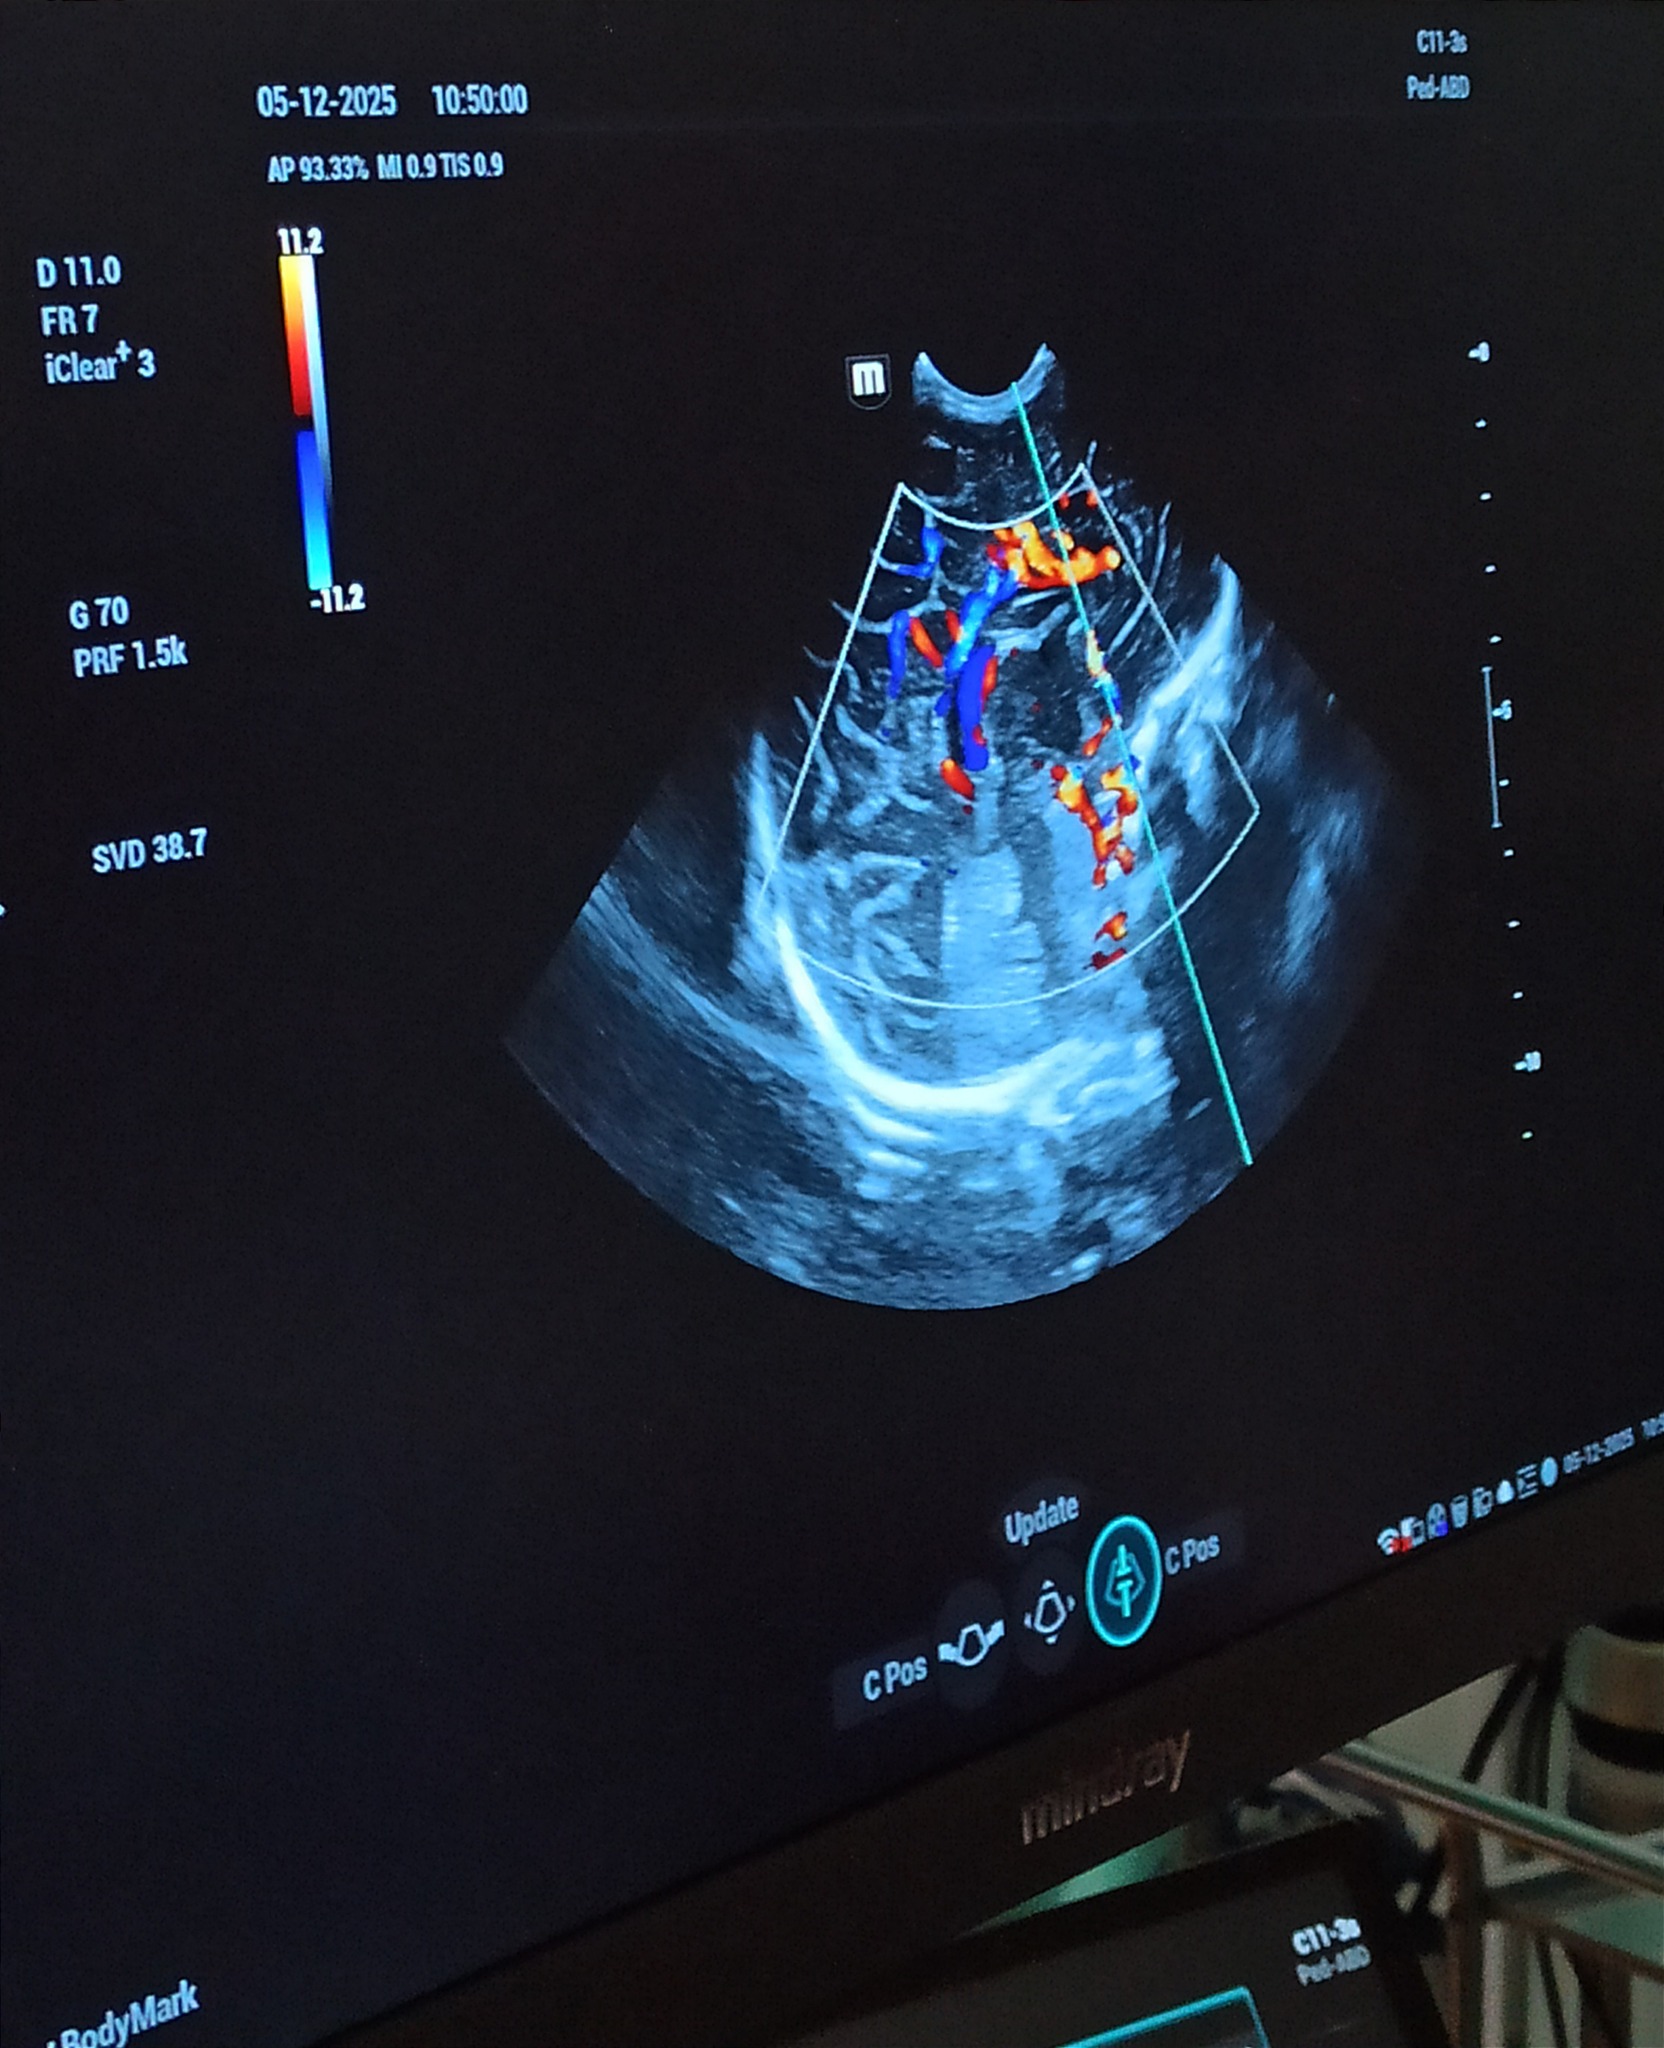

To zdecydowanie lepszy sprzęt niż ten, którym dysponowaliśmy dotychczas – podkreśla Wojciech Kowalik, lekarz kierujący oddziałem. – Urządzenie posiada cztery specjalistyczne głowice przeznaczone wyłącznie do badań noworodków: do badań echokardiograficznych, główki, jamy brzusznej oraz stawów biodrowych. Jest również wyposażone w doskonały program naczyniowy do obrazowania naczyń mózgu, jamy brzusznej i serca – dodaje.